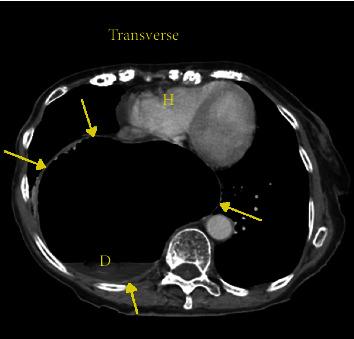

Hiatal hernia is a not uncommon anatomic disorder resulting in portions of the bowel occupying space in the thoracic cavity. There are a number of antecedent risk factors including obesity but not hiatal hernias resulting in symptoms. When symptoms do occur, they can include chest pain, nausea, abdominal pain, and gastroesophageal reflux. Cardiac arrhythmias have also been reported as associated conditions resulting from a hiatal hernia. To date, however, a complete heart block secondary to a hiatal hernia has not been reported. An 88-year-old female with a history of GERD (gastroesophageal reflux disease) was found to have a large hiatal hernia at endoscopy after she presented to the emergency department with nausea and abdominal pain. Prior to her scheduled surgical repair, she developed symptomatic third degree heart block which resolved with nasogastric tube deflation of the gastric contents. After surgical repair of the hiatal hernia, she developed episodes of atrial fibrillation with rapid ventricular response and was started on diltiazem. She eventually converted back to normal sinus rhythm and remained dysrhythmia free. In addition to other known arrhythmias associated with hiatal hernia, a complete heart block can also be seen. Acute management requires deflation of the chest occupying hernia. This appears to be the one of the first reported cases of complete heart block caused by hiatal hernia.

食管裂孔疝是一种较为常见的解剖学疾病,可导致部分肠管占据胸腔空间。有许多相关危险因素,包括肥胖,但食管裂孔疝并不一定会引发症状。当出现症状时,可能包括胸痛、恶心、腹痛和胃食管反流。心律失常也被报道为食管裂孔疝的相关病症。然而,迄今为止,尚未有因食管裂孔疝导致完全性心脏传导阻滞的报道。一名88岁有胃食管反流病病史的女性,因恶心和腹痛到急诊科就诊,在内镜检查时发现有巨大食管裂孔疝。在预定进行手术修复之前,她出现了有症状的三度心脏传导阻滞,通过鼻胃管排出胃内容物后得以缓解。食管裂孔疝手术修复后,她出现了伴有快速心室反应的房颤发作,并开始使用地尔硫䓬治疗。她最终恢复为正常窦性心律,且未再出现心律失常。除了与食管裂孔疝相关的其他已知心律失常外,还可见到完全性心脏传导阻滞。急性处理需要使占据胸腔的疝内容物排空。这似乎是首例报道的由食管裂孔疝引起的完全性心脏传导阻滞病例。